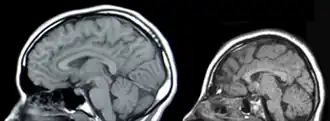

Unter einer Mikrozephalie (auch Mikrocephalie geschrieben; von griechisch μικρός mikrós „klein“ sowie κεφαλή kephalē „Kopf“) versteht man eine Entwicklungsstörung beim Menschen, bei der der Kopf eine vergleichsweise geringe Größe aufweist; der Kopfumfang ist hierbei drei Standardabweichungen geringer als der Mittelwert für einen Menschen gleichen Alters und Geschlechts.[1] Mikrozephalie geht für den Betroffenen mit einer geistigen Behinderung einher, deren Intensität vom Ausmaß und von den Begleitfehlentwicklungen abhängt. Die Häufigkeit beträgt 1,6 auf 1.000 Geburten.[2]

Gründe hierfür können eine Fehlentwicklung des Gehirns (Dyszephalie, Mikroenzephalie) oder ein vorzeitiger Verschluss der Schädelnähte (Kraniostenose) mit daraus folgender Dyskranie bzw. Mikrokranie sein.